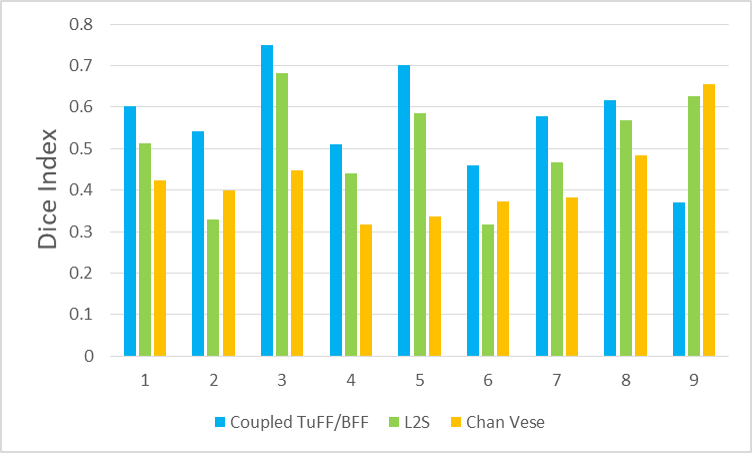

In our experiments, we compare the coupled TuFF-BFF microglia segmentation results with those given by L2S [21] and the Chan-Vese segmentation method [22]. The groundtruth in 3D was attained by manually tracing the object slice by slice from the z-stack. It must be noted that this was done by eye and could have some error. Figure 2 shows the visual comparison of the segmentation results for our dataset. Our result shown on the third column captures both the soma and processes. Figure 3 shows the Dice coefficient comparison of each segmentation method to the ground truth. Since the soma is much larger than the fine processes in the microglia, the processes have less volumetric impact on the similarity score. As explained in Section 1, segmenting the processes is important for quantifying the extension from the soma and its volume of surveillance. We use the Dice coefficient to quantitatively compare the ramification by taking the convex hull of the resulting segmentation. The Dice coefficient is a similarity measure that is computed using with where is the ground truth and is the compared image.

From Figure 4, the average Dice score for coupled TuFF-BFF was 0.77, compared to 0.53 for L2S [21] and .58 for Chan-Vese [22]. It must be noted that L2S required manual user initialization for each 2D image in the stack. While the Chan-Vese method has automatic seed selection, our coupled TuFF/BFF method was the only method that was a true 3D segmentation algorithm. L2S could not consistently capture the entire processes due to the intensity inhomogeneity throughout the object and background noise. The Chan-Vese segmentation could capture the extensions of the processes but did not work well with noise and attained false positives in the reconstruction. Since our method uses the tubular and blob information of the object to separate foreground and background, the segmentation only evolved within the object boundaries.